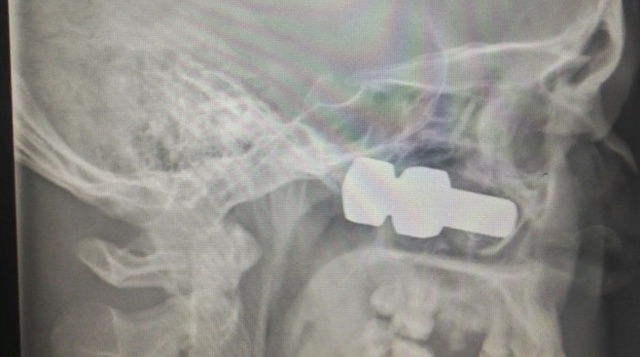

Мужчина получил мощный удар по голове и упал на землю. К счастью, остановился проезжающий мимо водитель легкового автомобиля, усадил пострадавшего в свою машину и довез до Лесосибирской городской больницы. Врачи обработали рану, а сделав снимки, увидели 6-сантиметровый болт, который находился внутри верхне-челюстной пазухи.

Врачи провели операцию и извлекли болт из головы. Медикам удалось спасти глаз пациента, но ему все же придется пройти курс лечения в краевом офтальмологическом центре, чтобы полностью восстановить зрение.